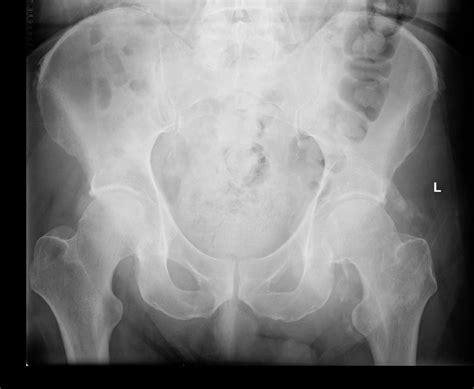

End Plate Sclerosis And Osteophyte Formation - Endplate sclerosis is a condition that affects the vertebral endplates, which are the thin layers of cartilage that separate the spinal discs from the. Endplate changes are traditionally characterized based on their mri appearance using the modic criteria and can be associated with bone sclerosis. Lumbar disc degeneration is characterised radiologically by the presence of osteophytes, end‐plate sclerosis and disc space narrowing.

Most prominent anterior vertebral osteophyte. 4.4 mm/16.4 mm = 0.27